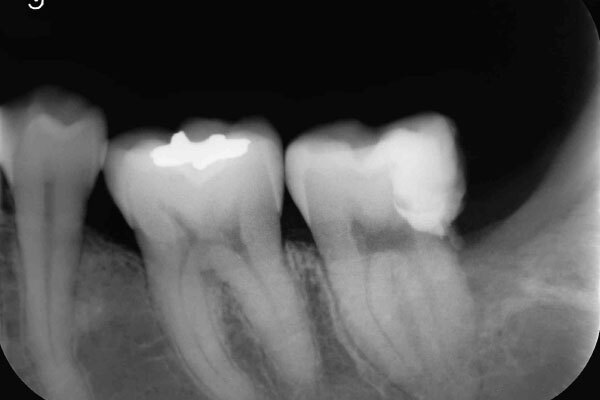

術前のデンタルX線写真と口腔内写真です。左下の一番奥の歯(#37)です。

左下の親知らずは1ヵ月ほど前に抜いたそうです。

親知らずと隣り合っていた歯の後ろ側(遠心)から虫歯が進行しています。

診査の結果、神経は正常に生きていることが分かりました。その為、いきなり神経は取らずに虫歯を取り切った上で神経を温存する治療を進めていくこととなりました。